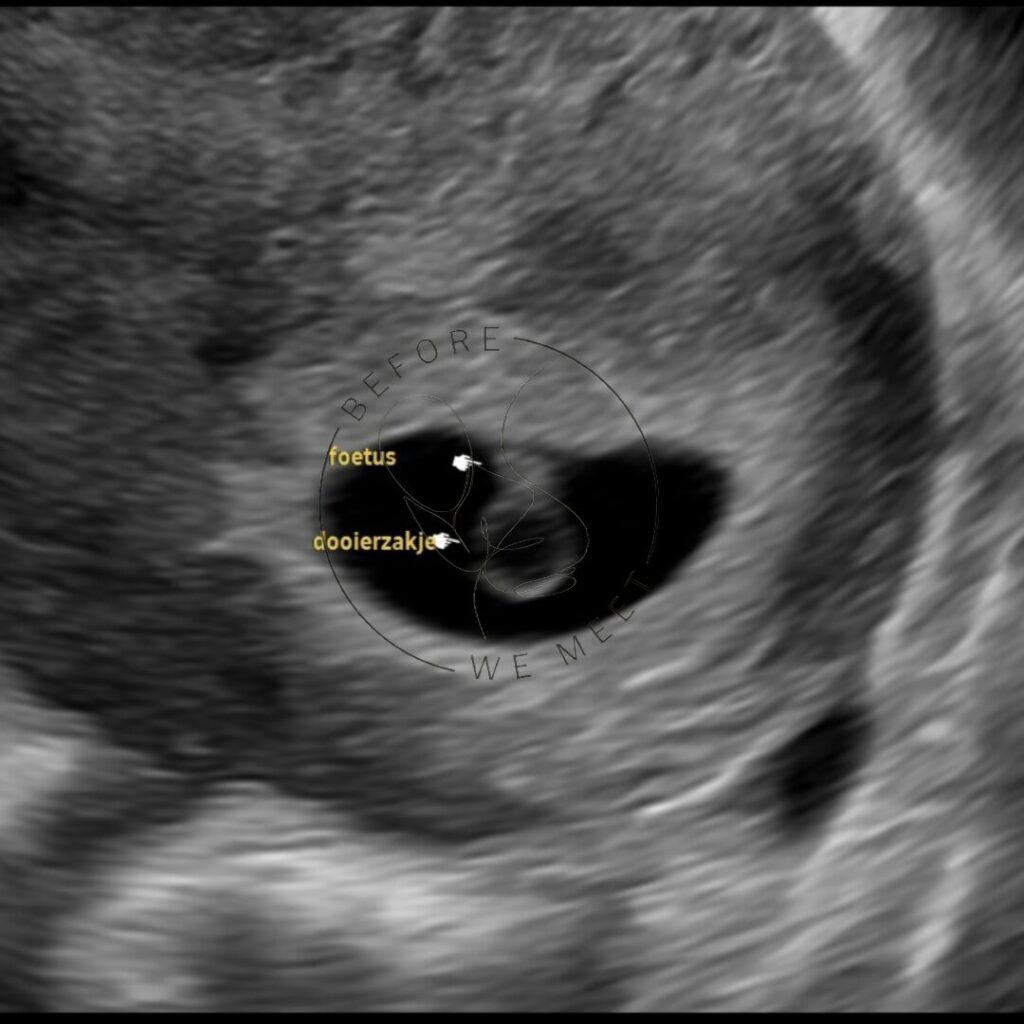

Vroege pretecho (tot 6+6 weken)

Onze vroege echo’s worden alleen uitgevoerd door onze medisch opgeleide echoscopisten. Wij meten de vruchtzak e.o. de baby op, zodat je weet hoever je zwanger bent. Bij deze echo bieden wij de mogelijkheid om inwendig te kijken.

Echo’s voor de 7 weken zwangerschap geven vaak het mooiste beeld wanneer we de echo inwendig maken, maar wordt natuurlijk alleen gedaan als jij hier toestemming voor geeft. Het maken van een inwendige echo is een medische voorbehouden handeling bij wet geregeld en mag alleen door een BIG-geregistreerde zorgverlener worden uitgevoerd. Dit betekent dat zij kennis heeft over de handeling en bijbehorend kan informeren. Onze echoscopisten die de vroege 2D echo uitvoeren zijn BIG-geregistreerd. Dit onderscheidt ons van veel andere pretechobureau’s. Je zal bij ons dan ook nooit het nieuws krijgen dat we de zwangerschap niet in beeld kunnen brengen.